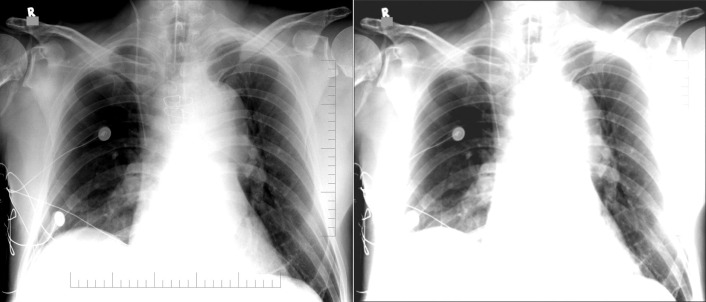

Central Venous Lines ( Figs. 22-1 to 22-13 )

To avoid mechanical irritation (from the catheter tip) and chemical irritation (from infusate) of the right atrium, the catheter tip of a central venous line should be further than the junction of the internal jugular vein and subclavian veins (near the level of the first thoracic rib). In addition, the tip should not be further in than the junction of the superior vena cava and right atrium. Central venous catheters that are intended to record central venous pressure should lie distal to the last venous valves (in the subclavian and internal jugular veins, 2.5 cm proximal to the beginning of the brachiocephalic vein) and before the right atrium. The ideal position of the tip of a peripherally inserted central catheter (PICC) line is in the distal superior vena cava.